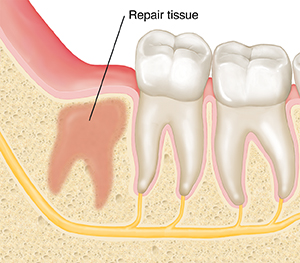

Healing after wisdom teeth removal usually takes a few months. First, a blood clot forms in the socket where the wisdom tooth was removed. This blood clot needs to stay in place to protect the bone and nerves. Within a day or two, the socket starts filling with repair tissue. This lays the foundation for new bone tissue to grow. When new bone tissue fills the socket, healing is complete.

| About 3 weeks after surgery, repair tissue has filled the socket. |